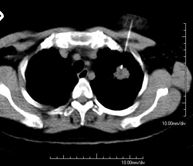

Prova que consisteix en obtenir una mostra de teixit de lesions toràciques, com per exemple masses pulmonars, mediastíniques, lesions òssies, etc. Per això s'administra anestèsia local sobre la zona de punció, que es realitza amb agulles de calibre fi. Tot el procediment es realitza controlat amb imatges obtingudes per tomografia computaritzada (TC) en diversos moments de la punció, mitjançant un equip de Fluoroscòpia-TC. Després de la prova, el pacient resta unes hores hospitalitzat. És necessari portar proves de coagulació abans de la punció. - CT-guided thoracic biopsy

It consists of obtaining a tissue sample from a specific thoracic lesion, such as the lung, mediastinum, sternum, etc. It is sometimes performed under sedation with the help of an anaesthesia team. Needles are used to draw a cylinder sample from the lesion to be studied, which is then sent to the Pathology Department for histological analysis. The entire procedure is performed with guidance from images obtained by computed tomography (CT) at various stages of the biopsy, using fluoroscopy-CT equipment. After the test, the patient remains in hospital under observation. Coagulation tests must be performed before the puncture.